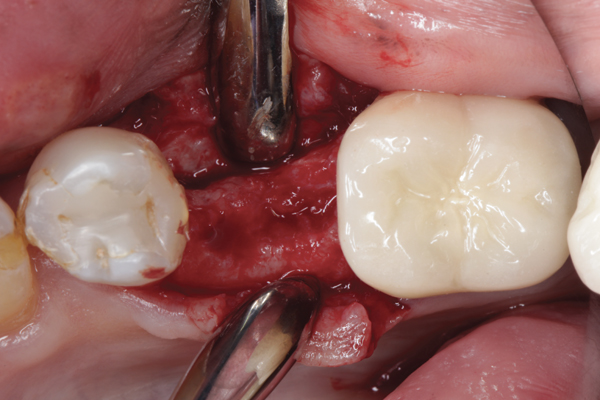

Fig 2. Buccal flap elevated exposing buccal plate defect.

Figure 2